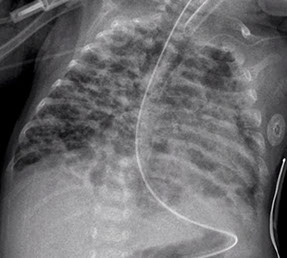

Severe BPD

BPD

Bronchopulmonary Dysplasia (BPD)

Bronchiolitis obliterans (necrotizing bronchiolitis) seen in acute phase

Chronic phase shows submucosal fibrosis, mucous gland atrophy, and squamous metaplasia